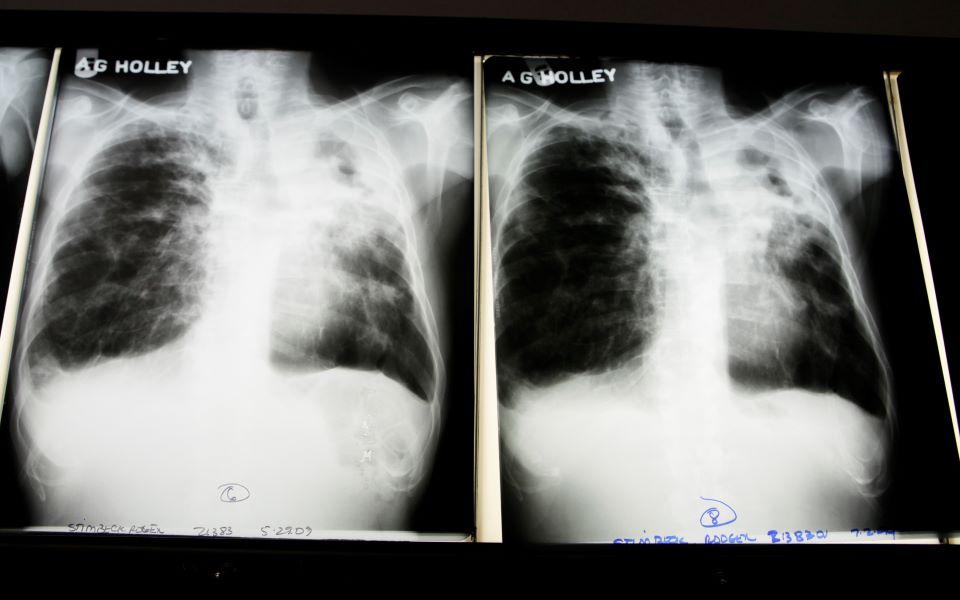

Nέα ευρήματα για τη φυματίωση: Μεταδίδεται περισσότερο με την αναπνοή από ό,τι με τον βήχα

Ανατρέποντας ένα ιατρικό δόγμα αιώνων, Νοτιοαφρικανοί επιστήμονες βρήκαν ότι η αναπνοή συμβάλλει περισσότερο από τον βήχα στην εξάπλωση της φυματίωσης.